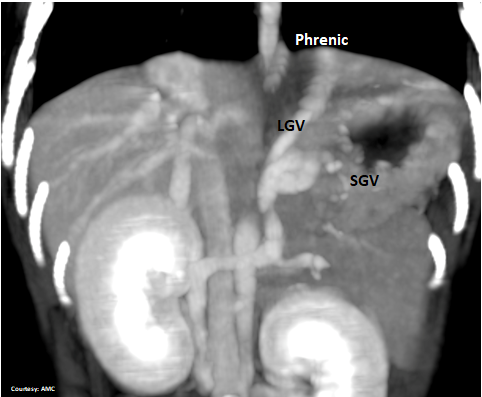

Does the SHORT GASTRIC VEIN (SGV) contribute blood to the shunt?

Does the LEFT GASTRIC VEIN (SGV) enter the GASTROSPLENIC VEIN (GSV)?

Does the GASTROSPLENIC VEIN (GSV) enter the PORTAL VEIN (PV)?